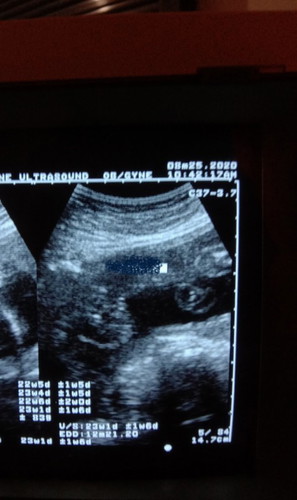

GUESS THE GENDER

What do you think? Girl or boy? 😁